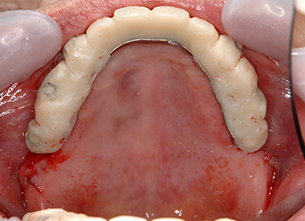

症例1 : 上下顎無菌顎症例

69歳、男性。

• 上顎は両側サイナスリフトと同時に即時荷重を行った。

• 下顎は抜歯即時埋入即時荷重を行った。

• 最終補綴物は、チタンのP.I.B.とM.B.のコンビネーションで修復した。

• 本症例の要旨は第39回日本口腔インプラント学会(大阪)にて症例報告した。